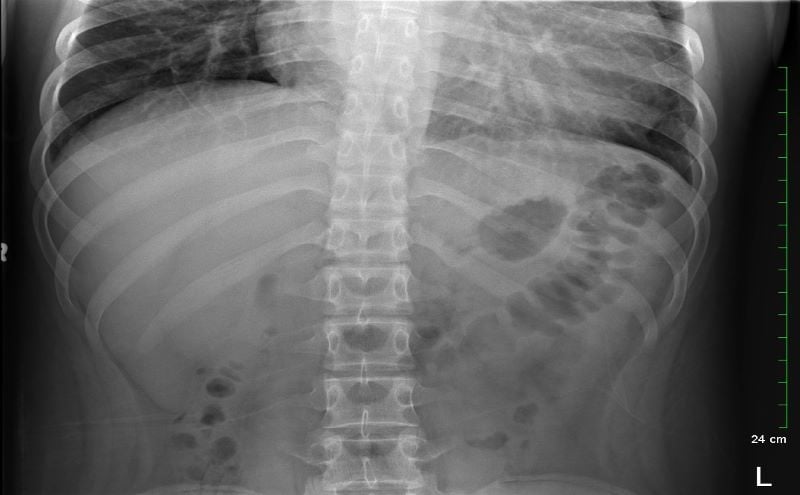

Because the patient presented with prolonged vomiting, a complete blood count (CBC), comprehensive metabolic panel (CMP), lipase, and kidney, ureter and bladder (KUB) was obtained. Initial labs showed only mild transaminitis and metabolic acidosis (AST 106, ALT 188, HCO3 15). KUB revealed the following images:

KUB read as normal by radiology. However, because of the enlarged heart border found incidentally on KUB, troponin I (0.05 ng/mL), B-type natriuretic peptide (BNP) (2186 pg/mL), and chest x-ray (CXR) was obtained, which showed the following: